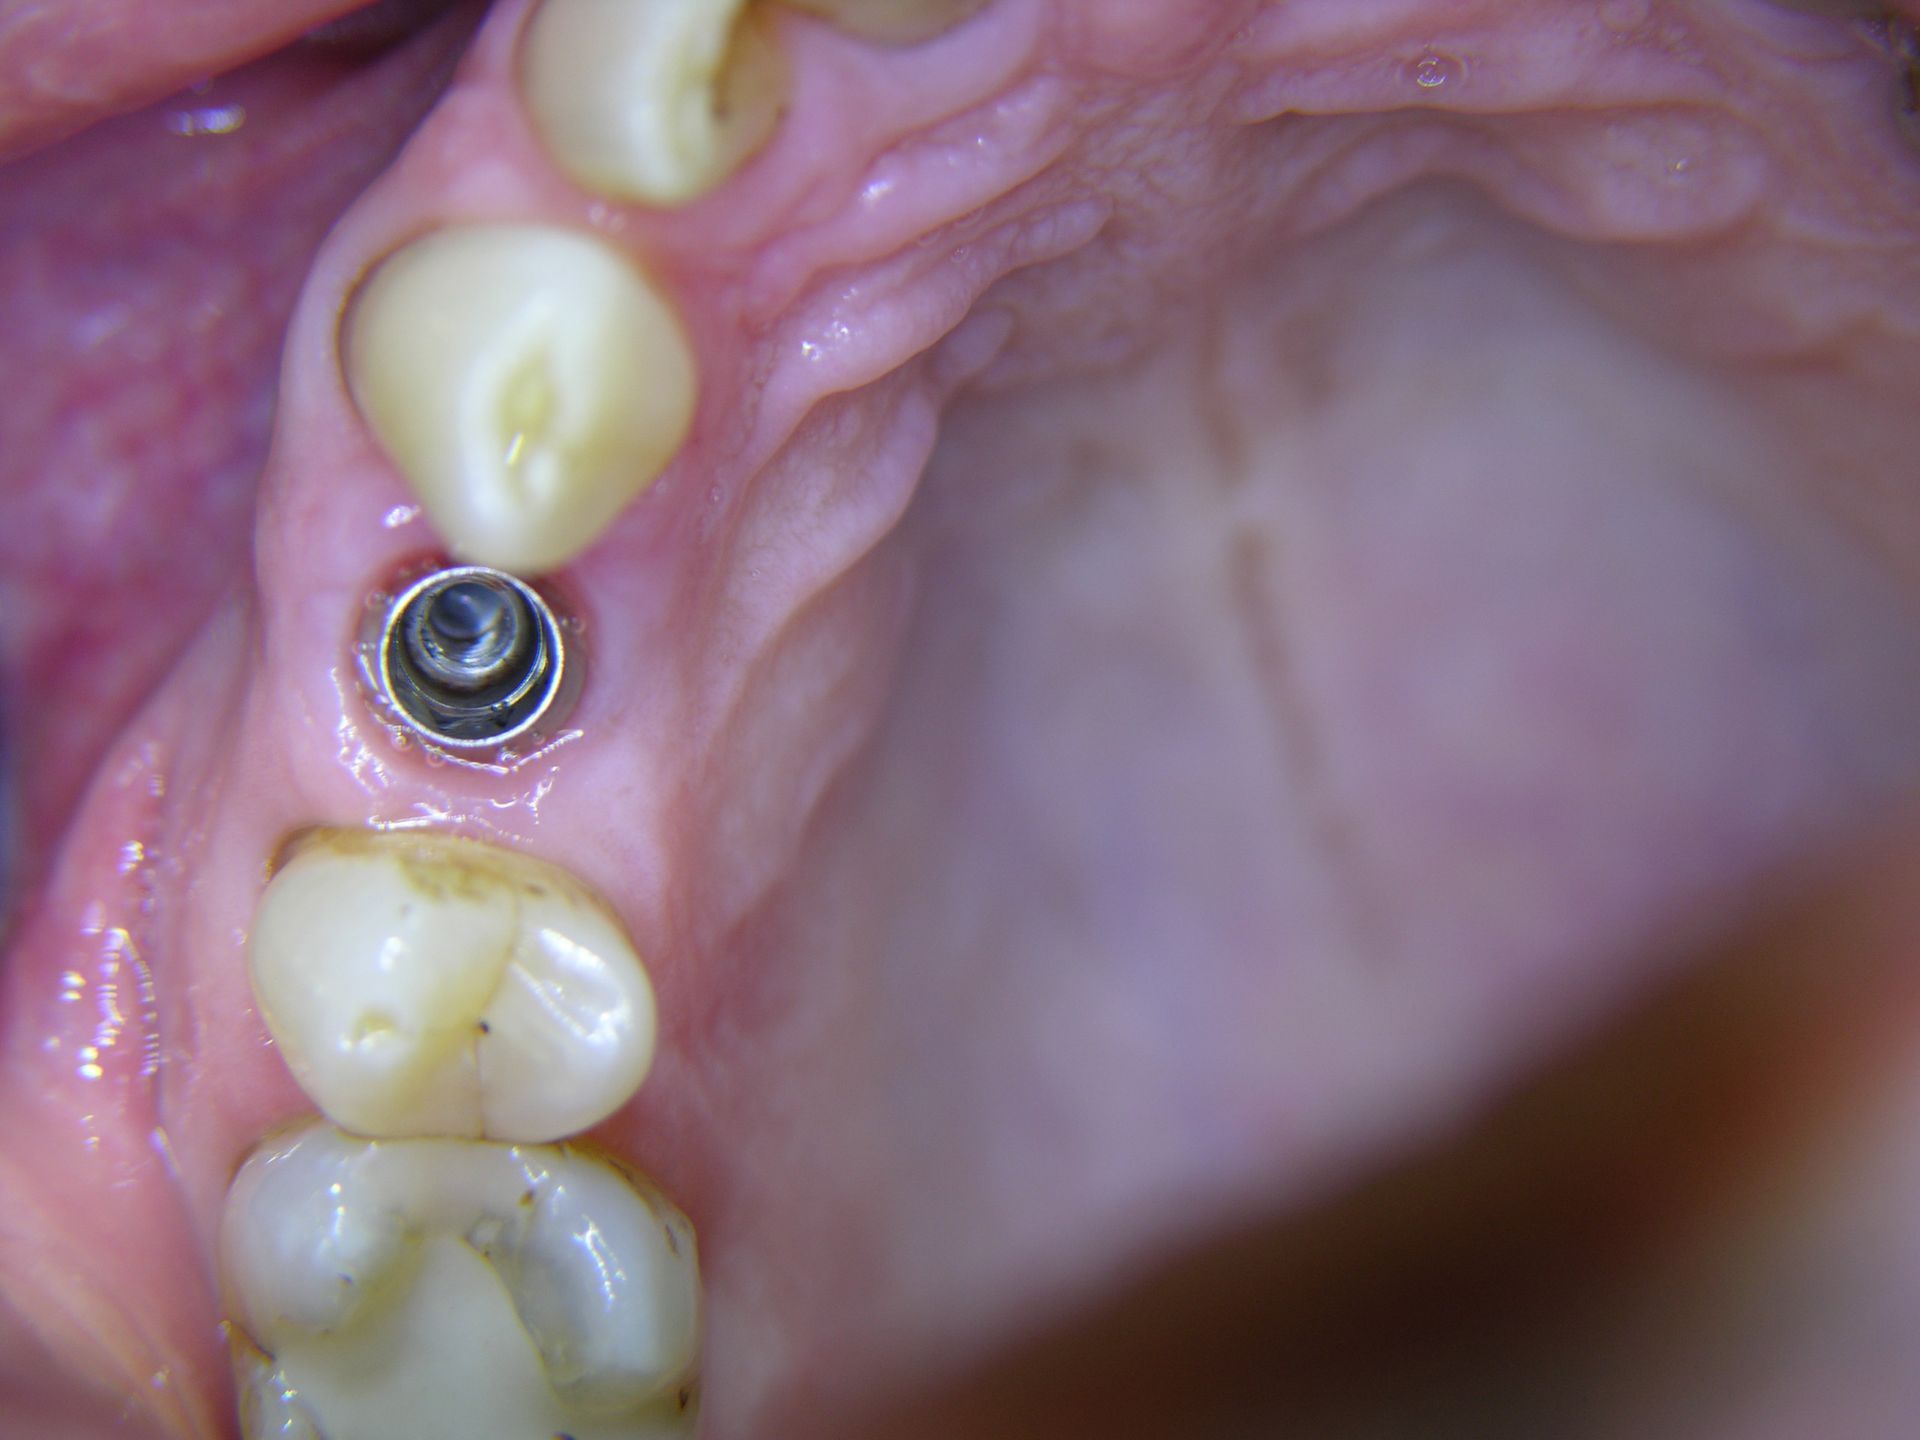

Beispiele von Versorgungen